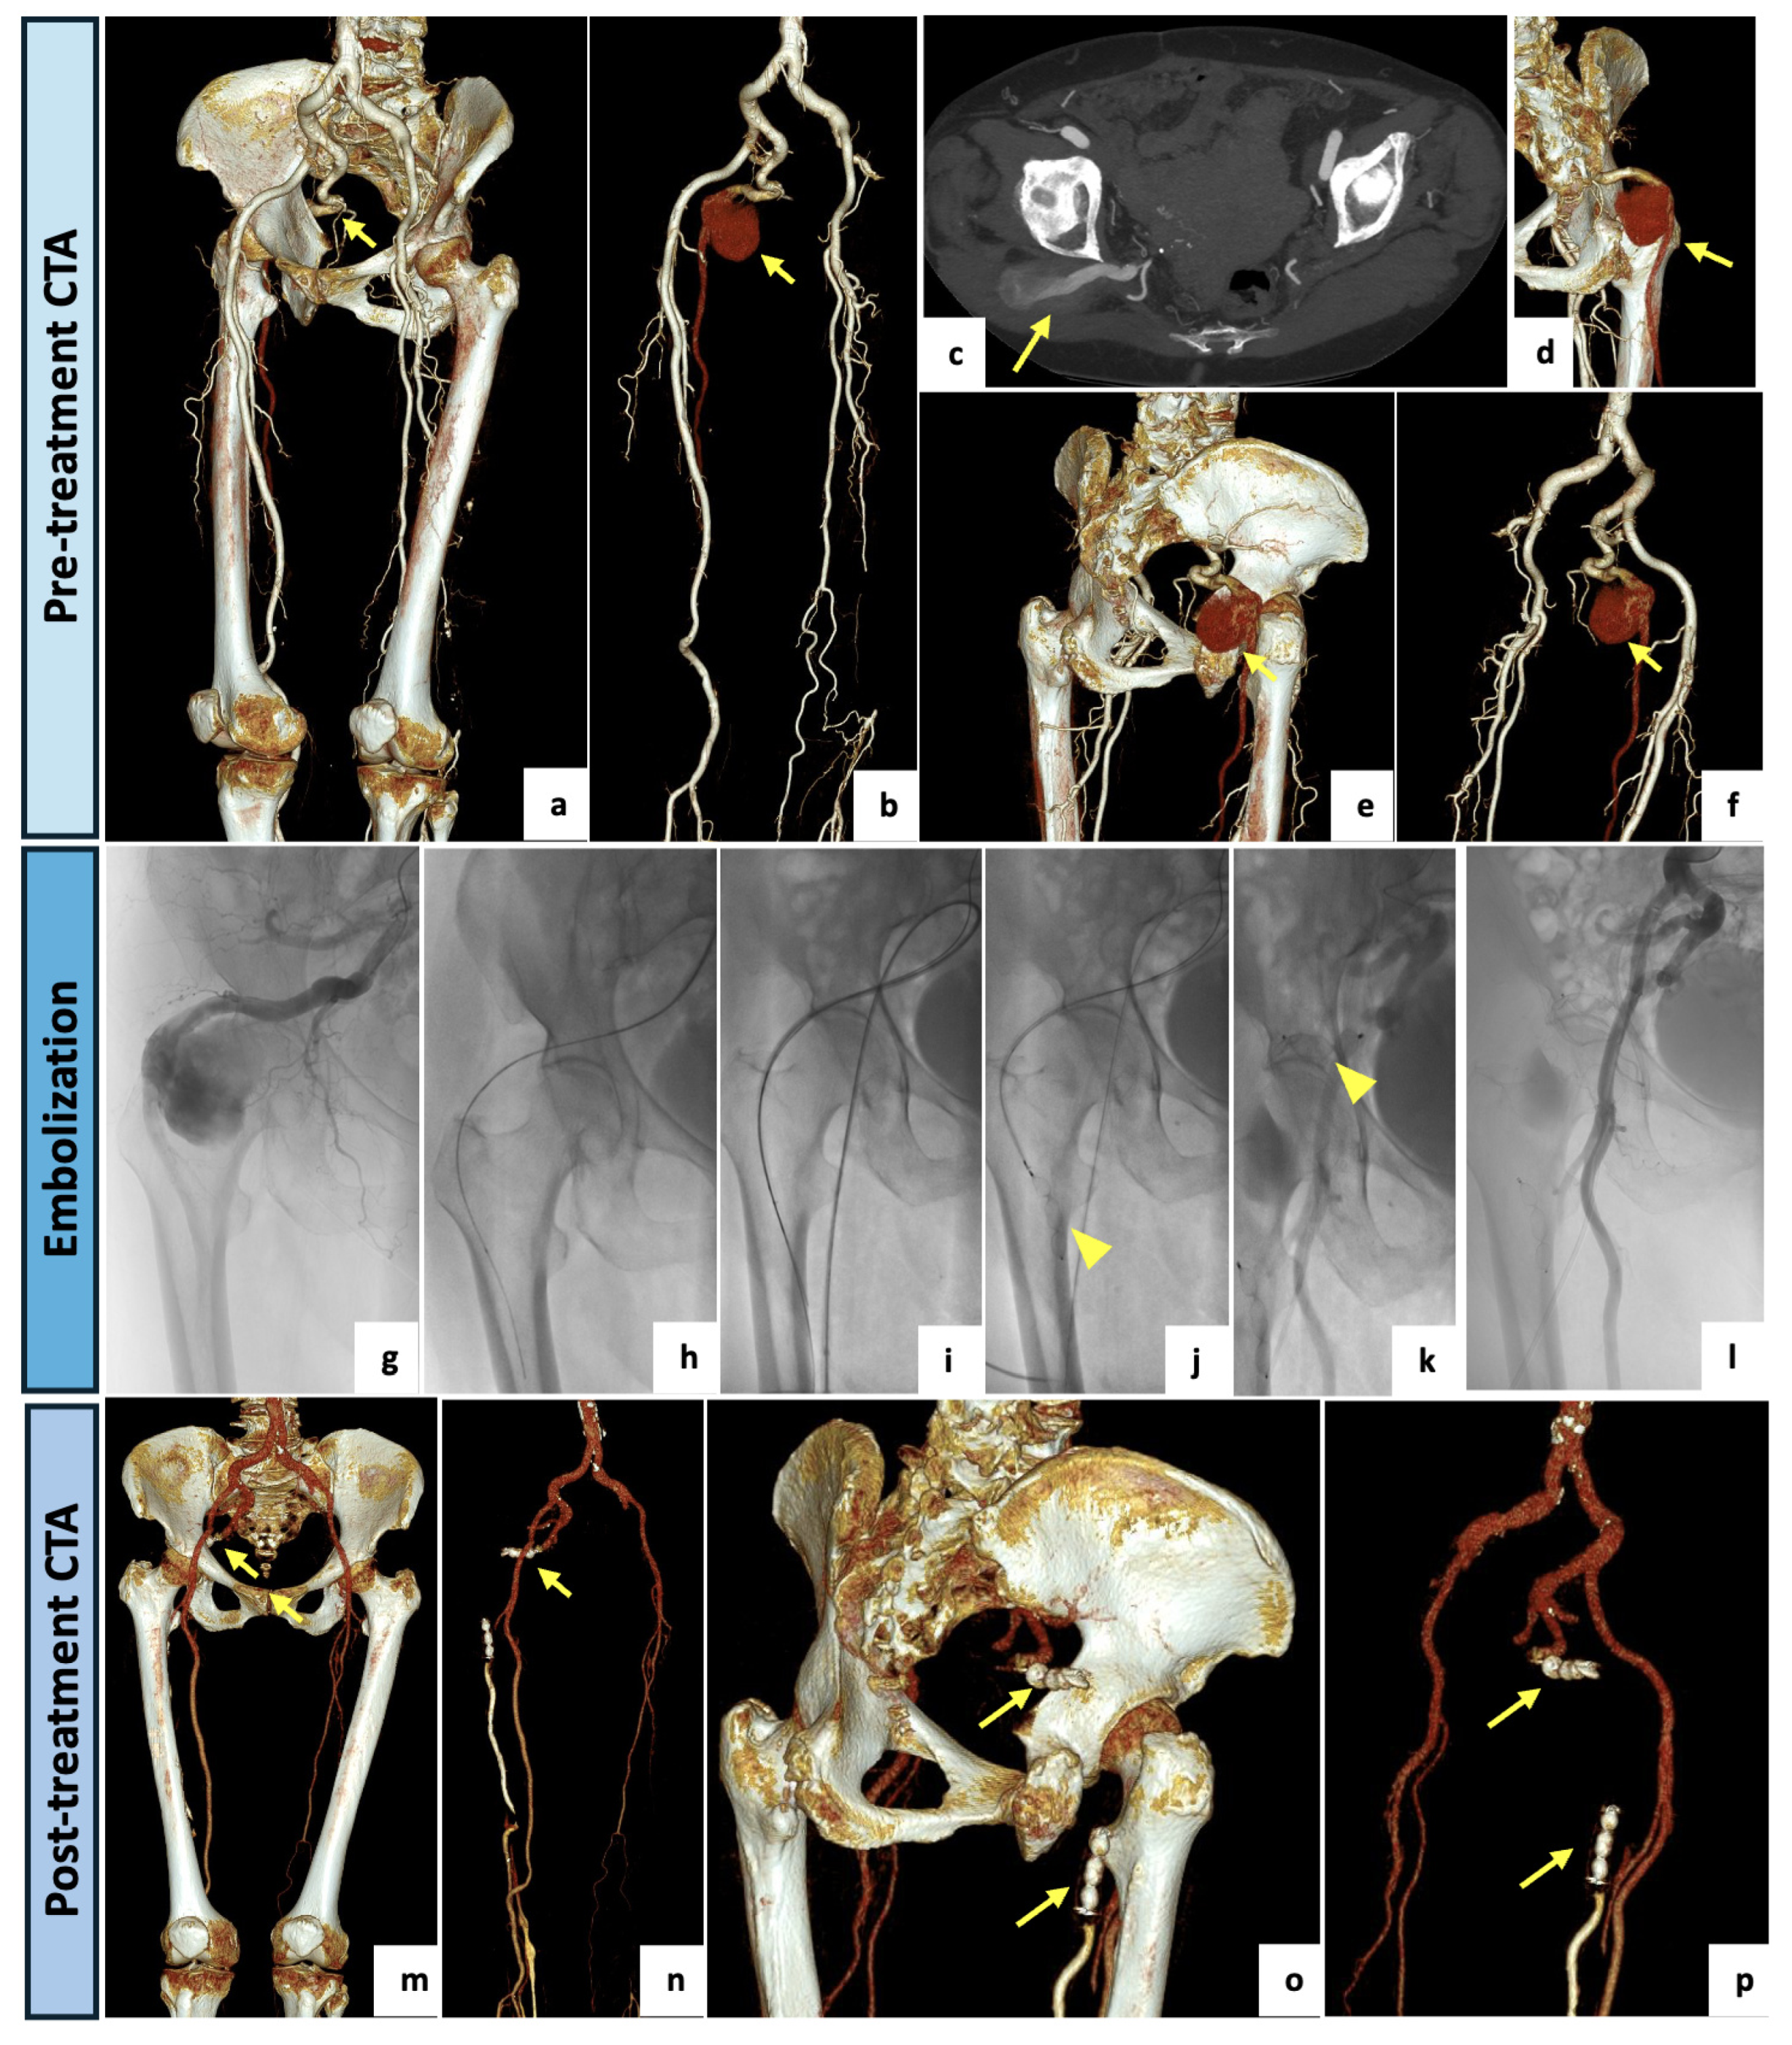

| 1 | 79 | Female | Right flank and buttock pain, burning sensation in gluteal region and in the back of right lower limb | CTA | Right limb: Type 1 with aneurysmatic PSA Left limb: Type 2a | Embolization with “sandwich technique” of right aneurysmatic PSA. | Clinical FU: complete disappearance of symptoms, no required pain medication. CTA FU (1-month): complete exclusion of PSA aneurysm. |